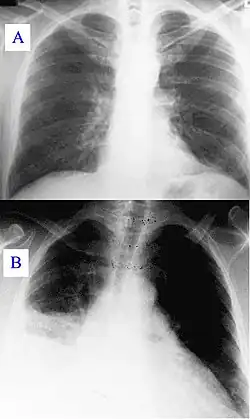

Основными методами диагностики являются рентгенологическое исследование лёгких и исследование мокроты, основным методом лечения — антибактериальная терапия. Поздняя диагностика и задержка с началом антибактериальной терапии ухудшают прогноз заболевания. В некоторых случаях возможен смертельный исход.

«Типичная» пневмония характеризуется резким подъёмом температуры, кашлем с обильным выделением гнойной мокроты и, в некоторых случаях, плевральной боли. При исследовании: укорочение перкуторного звука, жёсткое дыхание, усиленная бронхофония, усиленное голосовое дрожание, сначала сухие, а затем влажные, крепитирующие хрипы, затемнение на рентгенограмме. Такую пневмонию вызывают Streptococcus pneumoniae, Haemophilus influenzae, Escherichia coli, Klebsiella pneumoniae.

- Рентгенография грудной клетки